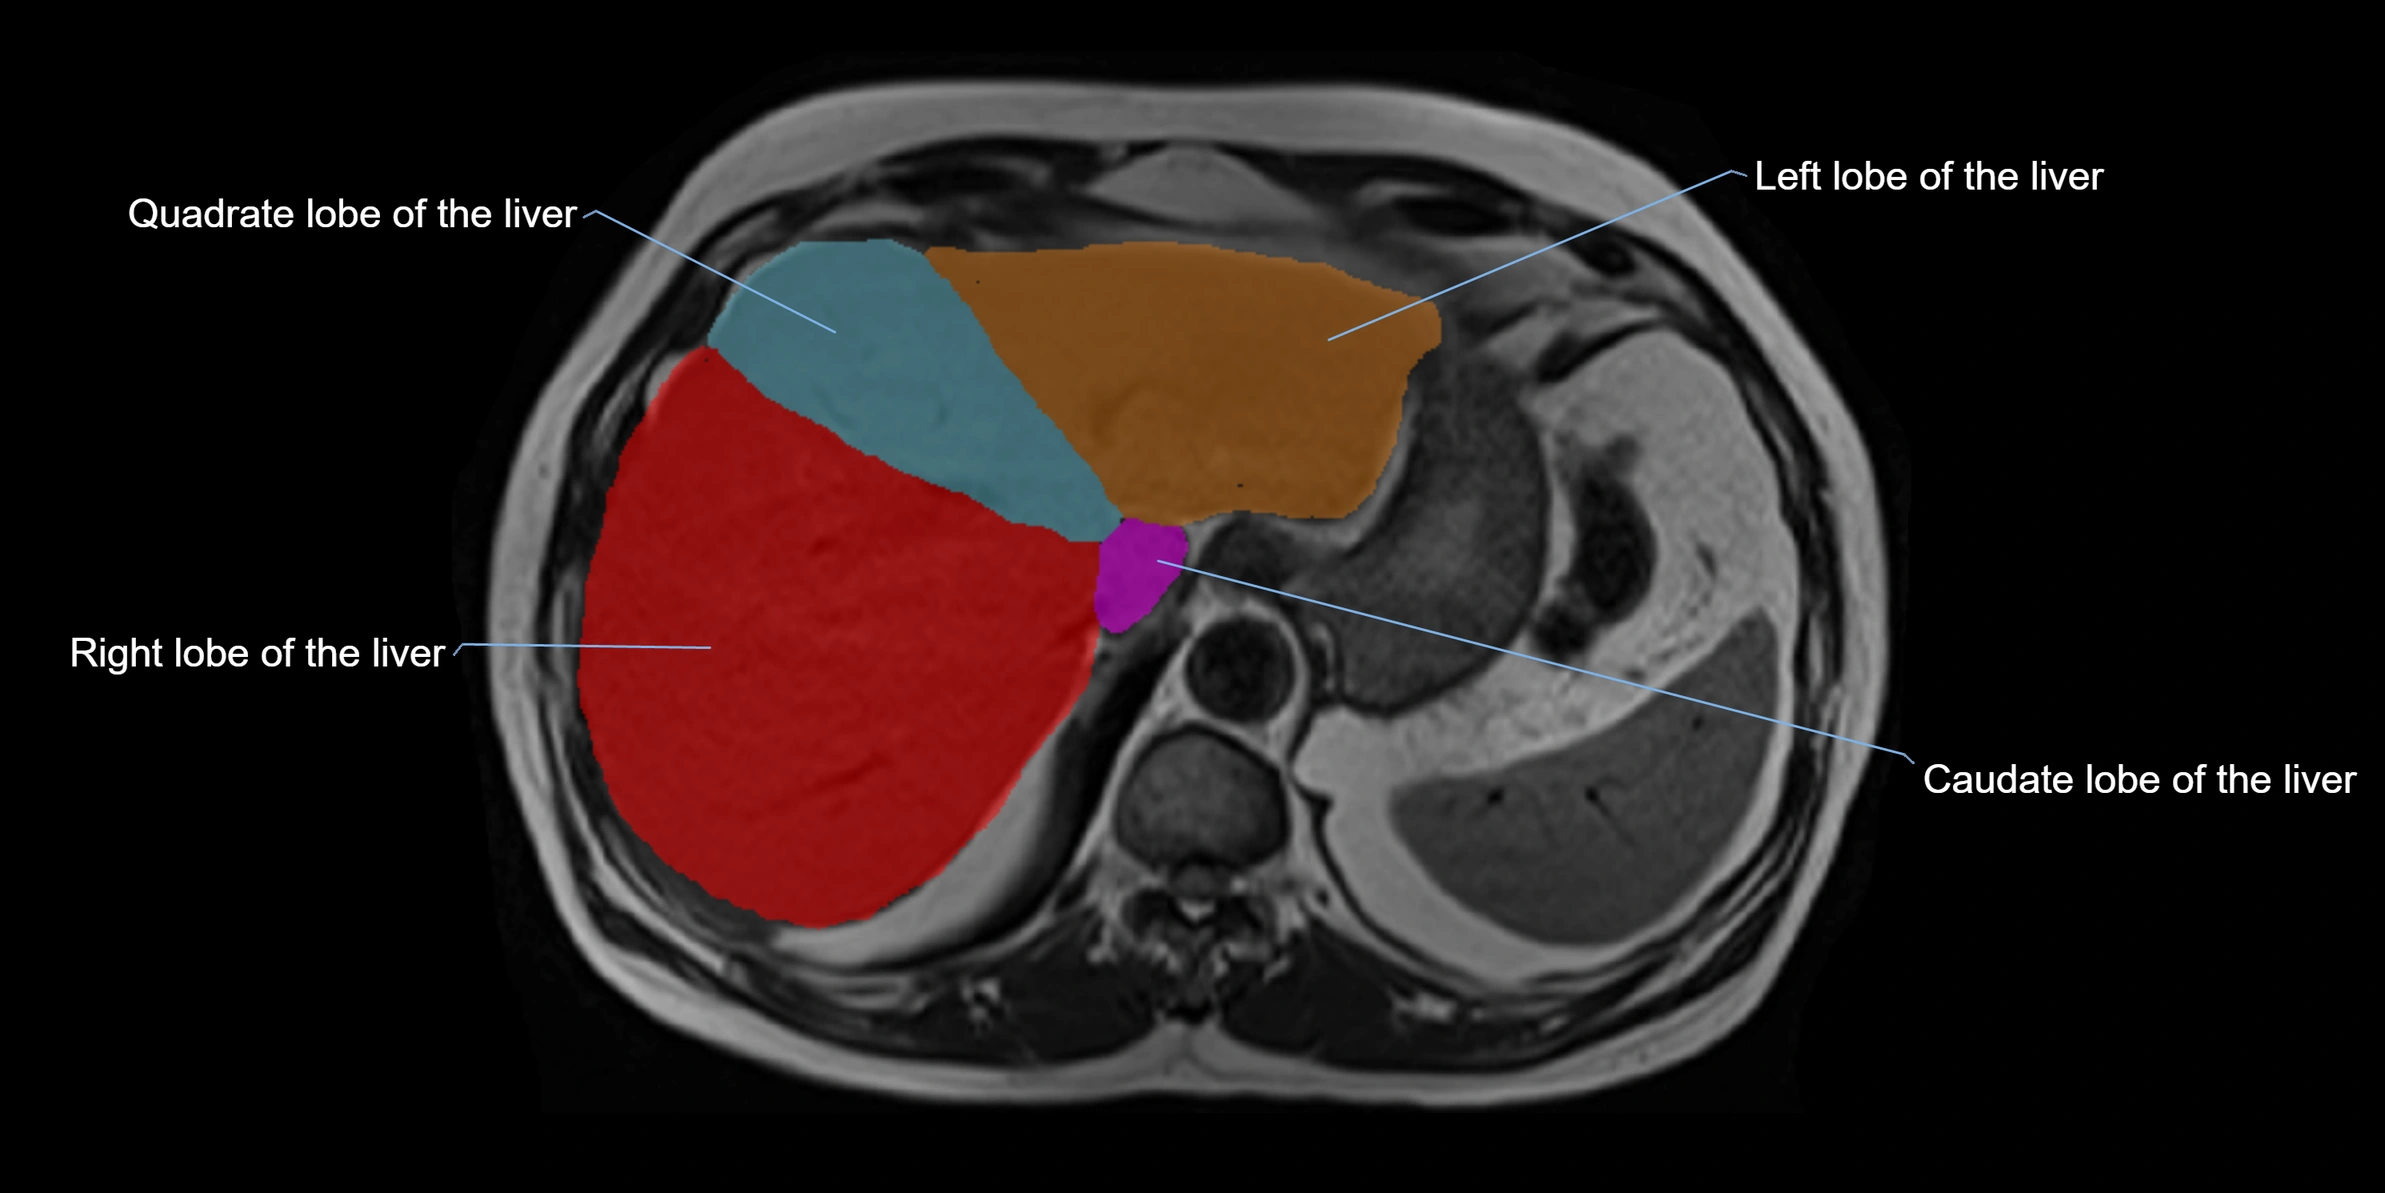

The caudate lobe of the liver is a distinct anatomical subdivision of the liver, designated as segment I in Couinaud’s classification. It lies on the posterior surface of the liver, between the fissure for the ligamentum venosum (left boundary) and the groove for the inferior vena cava (IVC) (right boundary). Superiorly, it is related to the posterior liver surface, and inferiorly it is separated from the left lobe by the porta hepatis.

The caudate lobe is unique because it receives dual portal venous and arterial inflow from both the right and left portal veins and hepatic arteries. It also has independent venous drainage directly into the IVC via multiple small hepatic veins, unlike other lobes that drain through the three main hepatic veins.

This anatomical autonomy makes the caudate lobe especially significant in liver surgery, transplantation, and hepatic venous outflow obstruction syndromes (e.g., Budd–Chiari syndrome). Enlargement of the caudate lobe is a characteristic imaging feature in chronic liver disease and cirrhosis.